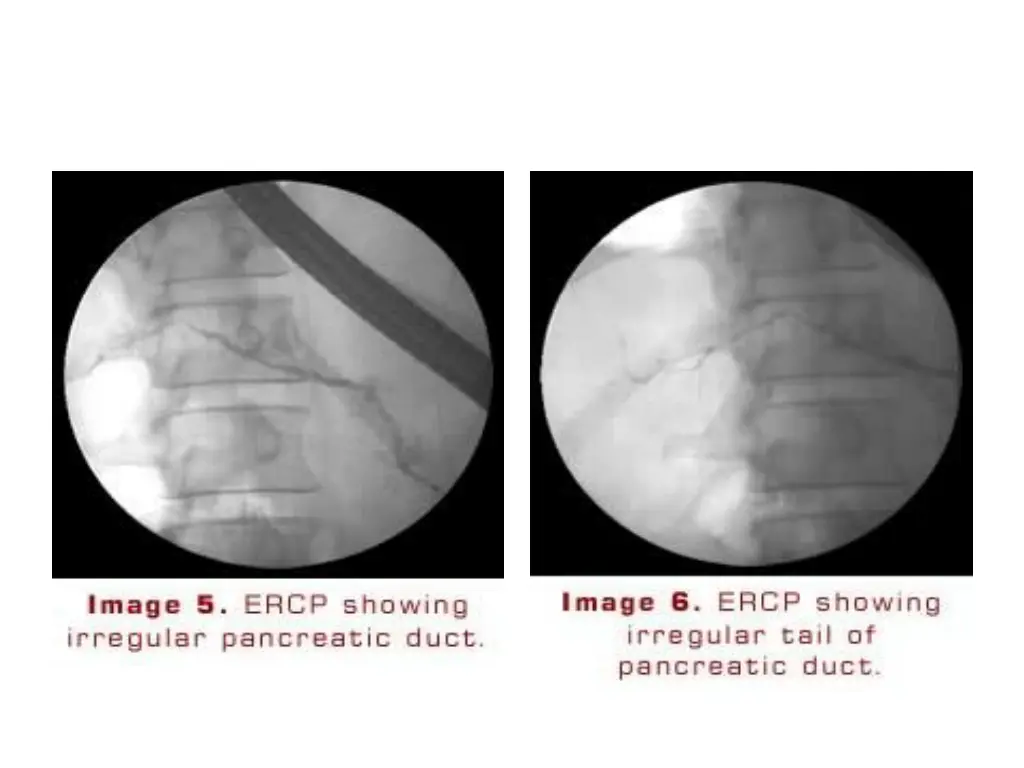

ERCP May provide useful information on the status of the pancreatic ductal system Abnormalities include : 1)luminal narowing 2)irregularities in the ductal system with stenosis, dilation,saculation,and ectasia 3)blockage of the duct by calcium deposits Endoscopic ultrasonography The most predictive endosonographic feature is the presence of stone